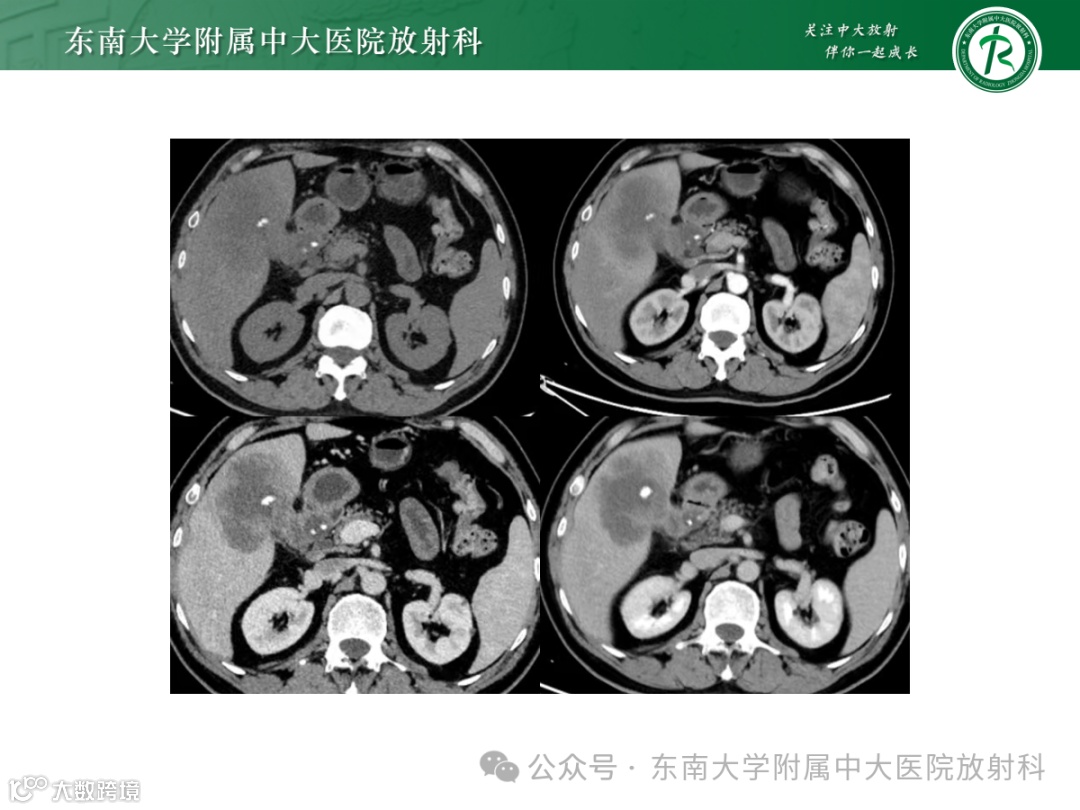

男,67岁 -

主诉:上腹部绞痛半月余 -

现病史:患者半个月前出现上腹部绞痛,夜间加剧,不伴发热,无寒战,无恶心呕吐,无腹泻,无反酸嗳气,无胸闷气喘,无呼吸困难,无黄疸 -

影像学表现